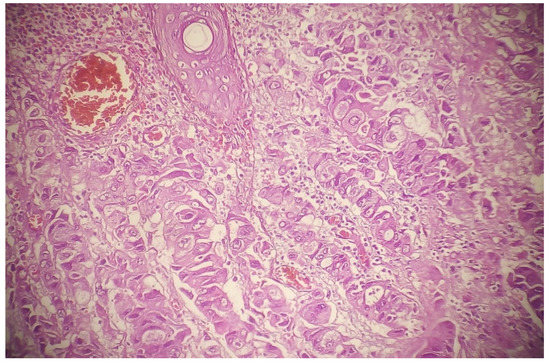

We retrieved the genetic data corresponding to 13 cases of ASCs and 15 cases of MACs of minor salivary glands. The histologic features of ASCs and MAC are shown in Figure 1. Figure 2 shows the genetic analysis of ASCs. What characterized the genetic profile are mutations in BCOR, CDH1, CEP57, ERCC4, GEN1, KLF4, LAMA5, MAC, MET, MN1, MTOR, NF2, PCLO, PRDM1, RB1, RELN, RIK3R1, SMARCB1, SOS1, and TP53 genes. Figure 3 shows the genetic network analysis for the possible interrelations between these genes. Cases of MACs showed mutations in AKT1. Regarding the immunohistochemical profile of ASCs, the squamous component stains with p63, p40, and cytokeratin 5/6.

3.2. Morphologic Difference in Different Sites

Most of the reported ASCs contained dense squamous congregations intermingled with true duct structures that showed cellular atypia. The stromal adenocarcinomatous component must be neither too superficial and inconspicuous (so as not to be considered an adenoid squamous cell carcinoma) nor very deep (so as not to be considered invasive SCC) (Figure 2). These cases are always considered high-grade. MACs are considered ASCs without an overlying SCC. For example, adnocarcinomatous lesions that secrete mucin and do not align with a particular recognized morphology (e.g., HG-MEC or high-grade mucinous cystadenomacinoma) are considered MACs. The indicated diagnostic immunohistochemical panel is rarely investigated. Figure 4 compares a case of MACs with a high-grade MEC of the minor salivary gland. Figure 5 shows a case of low-grade MAC of the lung. On the other hand, the ASCs of breast show both low-grade and high-grade features (Figure 6).

Figure 3. (Top) MAC of the minor salivary gland. (Bottom) MEC of the minor salivary gland.